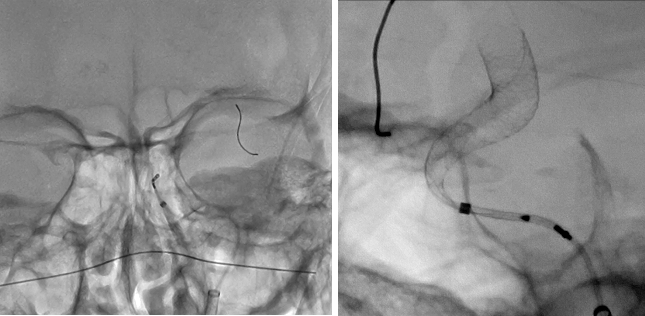

数字减影血管造影系统引导下的介入检查和治疗已成为心血管、神经血管及其它外周血管相关疾病的首选微创治疗手段。此次我院新引进的佳能ALPHENIX 凤凰9000V系统是第三代超高清数字减影血管造影系统,直接数字化平板探测器像素尺寸达到76微米,比传统设备图像精细度提高一倍以上,灰度显示达到16bit,比普通成像系统提高四倍,并可对细微结构进行大到20倍的光学显微放大,对于微小结构的小血管、微小介入材料和细微组织结构的可视性更高。

另外,双C臂机架一次完成两个角度造影,对复杂性血管结构显示达到立体化,在神经外科使用体现巨大优势。同时造影剂用量也大大降低,术中X线辐射量降低30%以上,手术时间显著缩短,特别适用婴幼儿手术。